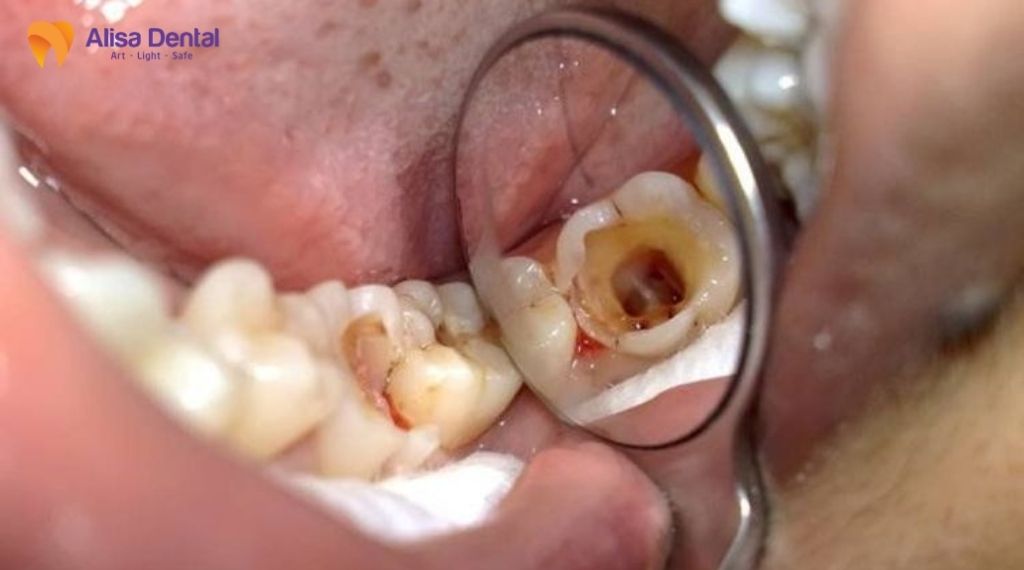

Trường hợp 1: Sâu răng nặng ăn vào tủy

Đây là nguyên nhân phổ biến nhất khiến bệnh nhân buộc phải tìm đến phương pháp điều trị tủy. Khi vi khuẩn tấn công, chúng sẽ phá hủy lớp men răng cứng bên ngoài, sau đó ăn mòn lớp ngà răng và cuối cùng xâm nhập vào buồng tủy – nơi chứa dây thần kinh và mạch máu.

Ở giai đoạn này, lỗ sâu thường rất lớn, có thể nhìn thấy bằng mắt thường (màu nâu hoặc đen). Vi khuẩn sinh sôi trong buồng tủy gây ra áp lực lớn, dẫn đến tình trạng viêm tủy không hồi phục. Bệnh nhân sẽ cảm thấy những cơn đau nhức dữ dội, đau buốt tận óc, đặc biệt cơn đau thường xuất hiện tự phát vào ban đêm khiến mất ngủ. Lúc này, việc trám răng thông thường không còn tác dụng, bác sĩ bắt buộc phải lấy sạch phần tủy đã nhiễm trùng để cứu giữ chiếc răng thật.